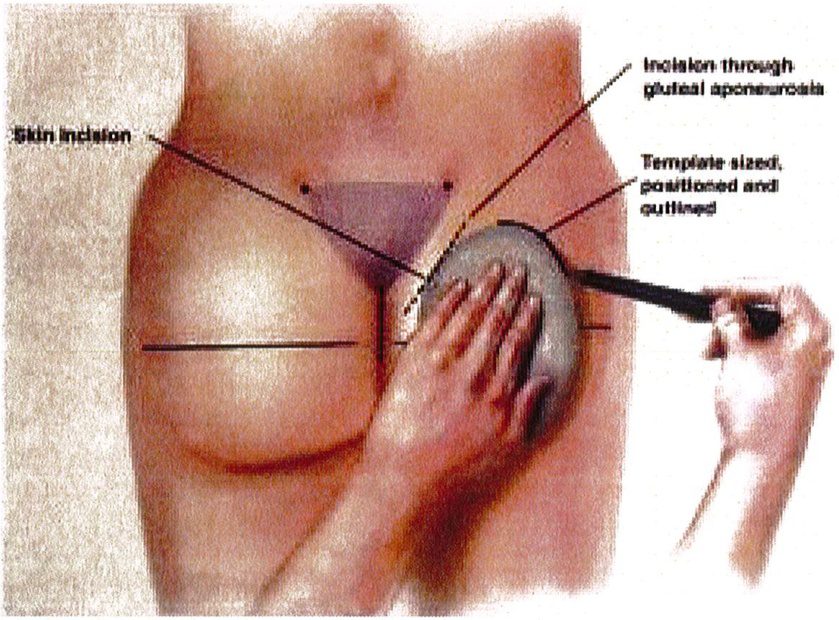

Sau khi tìm được tiêu bản phù hợp cho vùng mông mỗi bệnh nhân, dựa vào kích thước tiêu bản có thể dễ dàng xác định kích thước khối implant (hình 6). Kích thước khối implant nên được xác định trước phẫu thuật và xác nhận lại trong quá trình phẫu thuật (hình 7). Hiện nay đã có sẵn các khối im- plant được thiết kế với nhiều hình dạng và cấu trúc khác nhau, giúp chúng ta có thể dễ dàng lựa chọn.

Bệnh nhân ở tư thế đứng, đánh dấu vị trí khối implant theo

Hình. 6. Rạch da cạnh xương cùng, thực hiện bóc tách theo một góc nghiêng từ đường rạch tới giới hạn là đường bờ ngoài xương cùng. Sau đó tiếp cận tới lớp cân nông, rạch cân và đặt túi cấy dưới cân, trên bề mặt cơ mông lớn. (Trích từ de la Pena JA, Rubio OV, Cano JP, et al. Subfascial Nâng mông. Clin Plast Surg 2006;33÷411; đã xin phép trước khi đăng tải.)

Hình. 7. Đặt sizer lên trên vùng mông để ước lượng vị trí khối implant. (Trích từ de la Pena JA. Subfascial technique for Gluteal Augmentation. Aesthet Surg J 2004;24:268; đã xin phép trước khi đăng tải.)